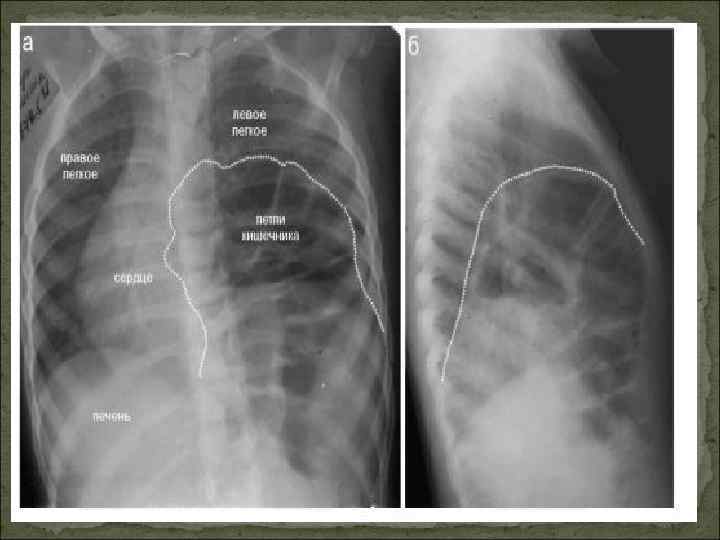

Внутренние Составляют 25 %. Внутрибрюшные Грыжи сальниковой сумки (ворота — foramen Vinsloe) Грыжи около сигмовидной кишки Грыжи около слепой кишки Грыжи около связки Трейтца, парадуоденальная грыжа (lig. duodenojejunalis) и другие внутрибрюшные образования Диафрагмальные ретрокостостернальные (справа — треугольника Морганьи, слева — Ларрея) пояснично-рёберные (Бохдалека) сухожильного центра диафрагмы (преимущественно — паракавальные грыжи) грыжи пищеводного отверстия диафрагмы (ГПОД): скользящие (аксиальные) и параэзофагеальные